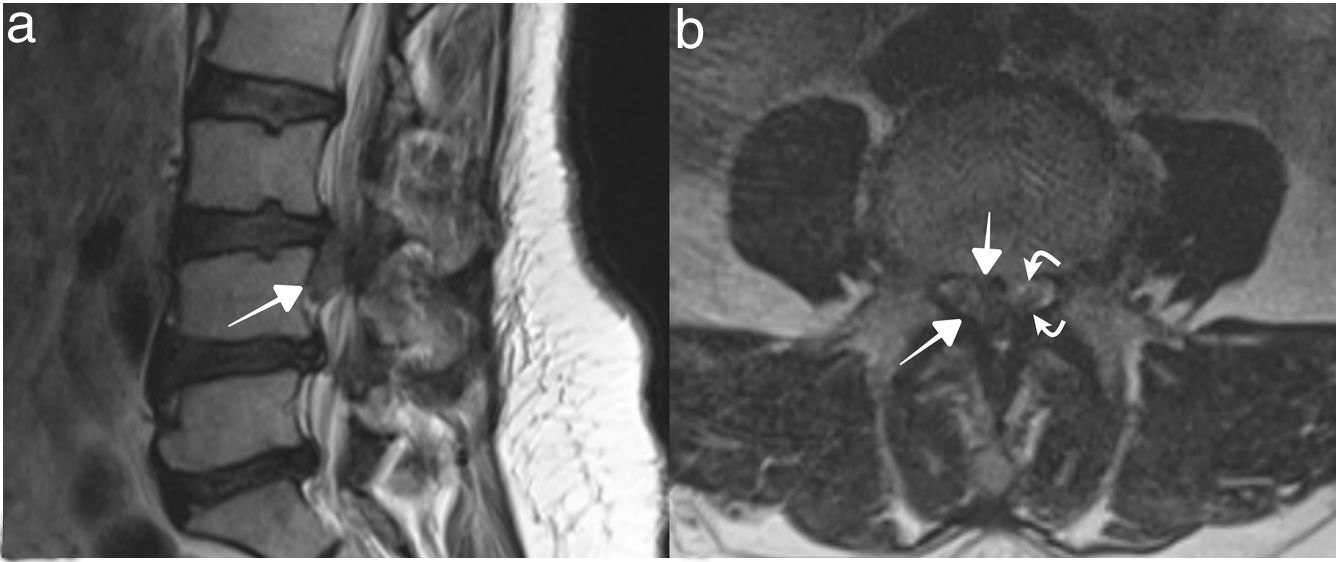

A cause of paraparesis in earthquake victim that possibly be overlooked: Traumatic massive lumbar disc herniation

Una causa de paraparesia en víctimas de terremotos que posiblemente pase desapercibida: hernia discal lumbar traumática masiva